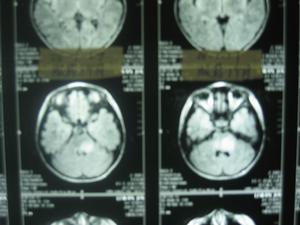

頭顱平片(正側位、顱底位)腦超聲診斷、腦電圖、顱腦CT檢查及心理測驗等。

2.3神經系統陽性體徵及腦CT、腦電圖24例(36.9%)發現有神經系統陽性體徵,其中共濟失調11例、巴賓斯基征陽性3例、局限性感覺缺乏4例、失語4例、肌張力改變2例。65例病人均在腦外傷後24小時內行頭顱CT或MRI檢查,發現異常43例(66.1%),其中腦挫裂傷21例、顱骨骨折6例、顱內血腫4例、蛛網膜下腔出血5例、硬膜下血腫7例。病灶主要位於額葉12例、顳葉10例、額顳葉2例、頂葉1例、枕葉2例。外傷後行腦電圖檢查60例發現異常42例,其中輕度異常21例,中度異常14例,重度異常7例。